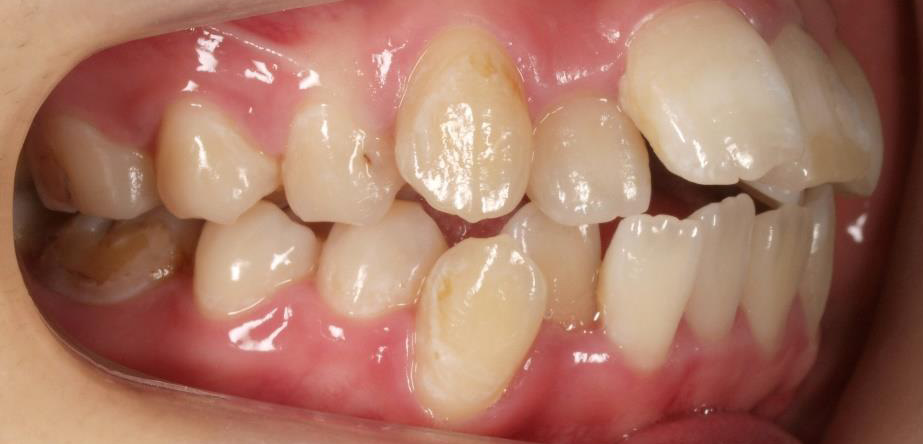

下顎が上顎より前に出ている状態です。お顔つきも、下顎の先(オトガイ)が前に出ているような横顔になる場合が多いです。前歯が咬んでいないことが多く、奥歯への負担が大きい状態になります。そのままのかみ合わせを続けてしまうと、奥歯がかけたり、割れたりするリスクが高まります。歯列矯正では奥歯の位置をコントロールし、前歯のかみ合わせを作る治療方針を立てます。ごく稀に、歯列矯正ではかみ合わせを作れない場合もあり、その場合は外科矯正という手段を用いて矯正治療をしなければいけません。受け口は、遺伝性が強いとも言われておりますので、そういった情報も考慮し、治療を進めていくことが大切です。

治療前

治療終了前